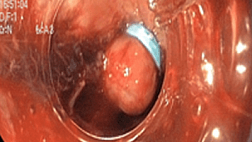

3.17. В случае необходимости проведения пациентам с COVID-19

(подозрением) эндоскопических исследований, персонал должен использовать полный комплект СИЗ как при проведении процедур, так и при обработке

эндоскопов. В целях обеспечения эпидемиологической безопасности вмешательств рекомендуется: для проведения предварительной очистки эндоскопа использовать только одноразовые емкости (стаканчики), растворы моющих и моюще дезинфицирующих средств для окончательной очистки использовать однократно, использовать для ручной и автоматизированной обработки средства дезинфекции высокого уровня обеспеченные тест-полосками, проводить контроль концентрации действующего вещества в растворе средства в начале каждого рабочего дня и перед обработкой эндоскопа, использованного для обследования пациента с острым респираторным синдромом. В целях предотвращения образования и разбрызгивания микробных аэрозолей в ходе предварительной очистки эндоскопа промывку каналов биопсия/аспирация проводить при закрытом биопсийном клапане (если колпачок клапана имеет отверстие от прохода инструмента, его необходимо заменить), замену клапана воздух/вода (где это предусмотрено производителем) на адаптер проводить после выключения регулятора воздушного потока на источнике света; при промывке каналов воздух/вода и дополнительного канала подачи воды под давлением дистальный конец эндоскопа следует опустить в емкость с небольшим количеством воды; при окончательной очистке проводить все манипуляции по механической очистке различных участков эндоскопа щетками в толще моющего раствора, при проведении сушки воздухом каналов очищенных эндоскопов закрывать места выходов каналов салфетками.